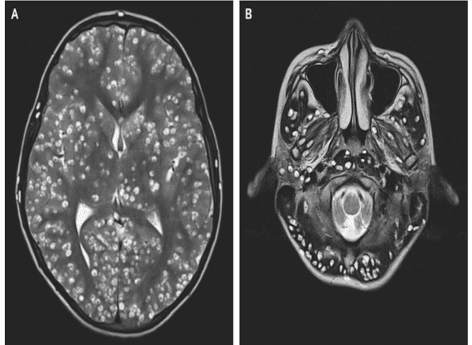

Des médecins ont découvert des dizaines de larves dans le cerveau d'un jeune homme de 18 ans. En dépit de leurs efforts pour le sauver, il a succombé à sa neurocysticercose deux semaines plus tard.

- Capture d'écran/nejm

Voilà une fin particulièrement tragique. En Inde, un jeune homme de 18 ans est mort d’une neurocysticercose, une infection parasitaire du système nerveux central. Concrètement, son cerveau était rempli de larves enkystées, rapporte la revue New England Journal of Medicine. Si cette affliction, une maladie tropicale touchant le plus souvent les populations défavorisées, avait déjà été observée, il s’agit ici d’un cas particulièrement extrême.

Ce sont les parents du malade qui l’ont conduit à l’hôpital de Faridabab. Car le jeune homme souffre énormément du côté de droit de l’aine et fait des crises d’épilepsie régulières, indiquent-ils aux médecins. Ces derniers lui font donc passer une IRM et une échographie. Ils découvrent alors que son cervelet, son tronc cérébral et son cortex cérébral sont plein de larves en train de s’enkyster. Le malheureux est également atteint à l'oeil droit et à la testicule gauche.

Diagnostic : le patient souffre de neurocysticercose, une infection infection parasitaire du système nerveux central provoquée par un ver plat appelé le ténia du porc (Taenia solium). Si cette maladie a déjà été observée par les médecins, elle est ici particulièrement avancée. Le jeune homme est si atteint que les spécialistes ne peuvent pas lui donner d’antiparasitaire de peur d’aggraver sa pression intracrânienne déjà très élevée. Dans l’espoir de réduire l’inflammation et de contrôler les crises d’épilepsie, ils lui prescrivent donc un corticoïde. En vain, le jeune homme est déjà bien trop atteint. Il décède deux semaines après sa visite à l’hôpital.